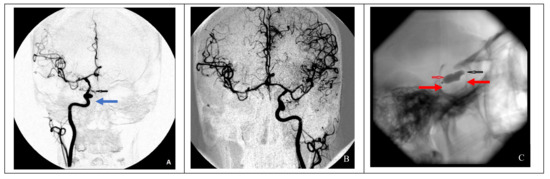

In cases of adequate collateral blood flow, endovascular occlusion at the ICA injury site using balloons in two cases and microcoils in three cases was performed (Figure 2).

Figure 2. Endovascular surgical treatment in cases with good collateral circulation (clinical case 2). (A) A false aneurysm in the area of the cavernous segment of the right ICA (indicated by the blue arrow), (B) cerebral angiography of the left ICA demonstrating good collateral blood flow to the contralateral side, and (C) occlusion of a defect in the right ICA using two balloons (indicated by red arrows).